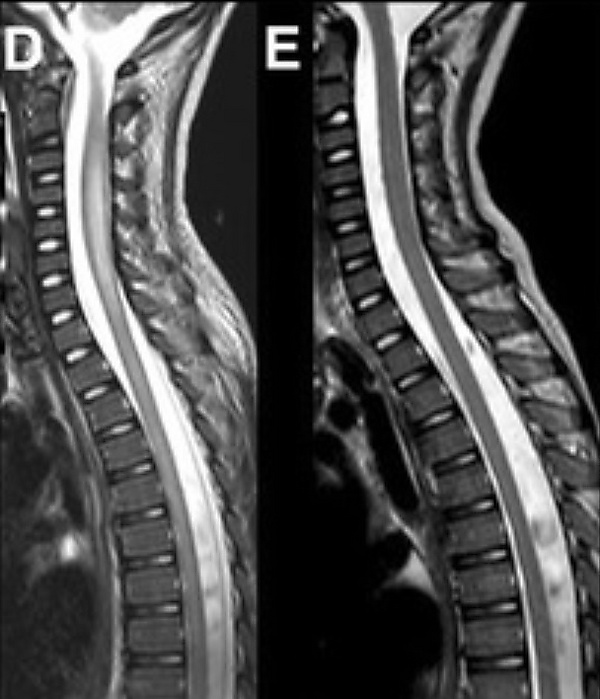

При проведении магнитно-резонансной томографии спинного мозга с контрастным усилением обычно выявляется обширное неконтрастируемое очаговое поражение в области передних рогов спинного мозга, которое проявляется повышением интенсивности сигнала на T2-взвешенных изображениях. Данное поражение часто распространяется на один или несколько позвоночных сегментов. У подавляющего большинства пациентов сигнальные изменения наблюдаются на всем протяжении спинного мозга. В острой фазе заболевания может также отмечаться перифокальный отёк[4].